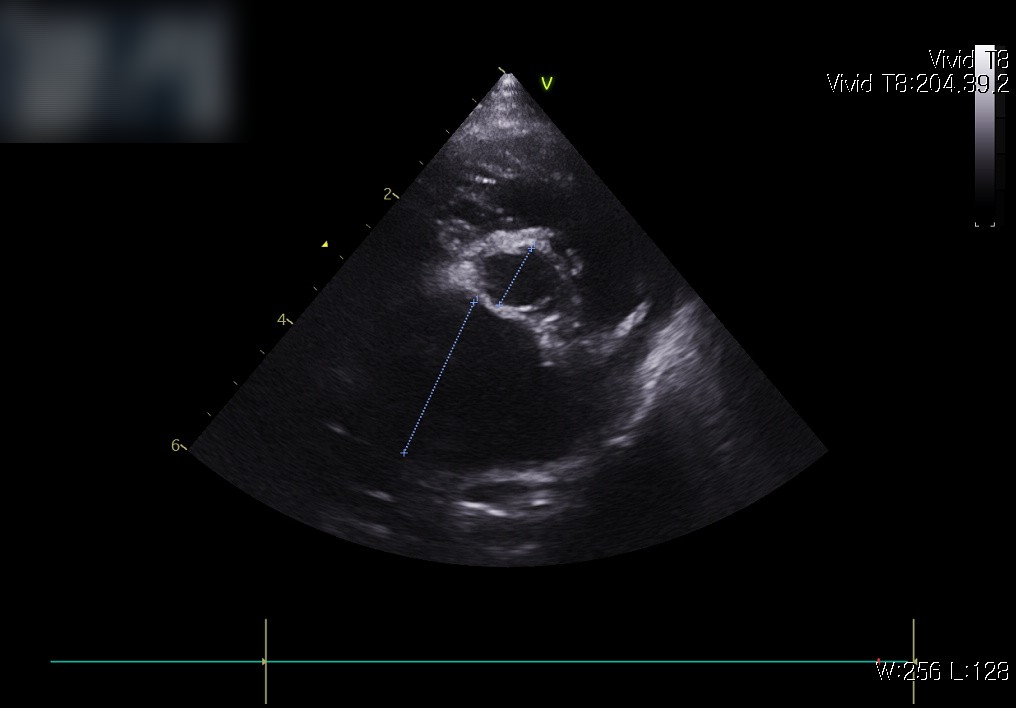

📌 심장 초음파

초음파 검사는 심장의 구조와 기능을 직접 확인할 수 있는 가장 중요한 검사입니다. 판막이 제대로 닫히는지, 심실 벽의 두께는 정상적인지, 혈액이 원활하게 흐르는지를 정밀하게 평가할 수 있습니다.

내원 즉시, 적극적인 산소처치와 안정화가 먼저 이루어졌습니다. 호흡곤란 환자는 응급 상황으로 진행될 수 있기 때문에, 빠른 산소 공급과 안정을 통해 위험을 줄이는 것이 최우선입니다. 이후 상태가 안정되자 심장 초음파와 흉부 방사선을 통한 정밀 진단이 진행되었습니다.

심장 초음파 사진: 판막 기능 이상과 혈류의 역류 소견 확인

검사 결과 심부전 소견이 확인되었고, 이에 따라 약물 관리를 통한 환축 안정화를 목표로 치료를 시작했습니다.